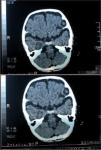

A las 30h de su ingreso presenta una temperatura de 37,5°C, se inician clonías del miembro superior derecho y desconexión con el medio, de 35min de duración, que precisó tratamiento con diazepam, fenitoína y midazolam. Se realiza tomografía computarizada (TC) craneal previa a una segunda punción lumbar, dada la desfavorable evolución que presentaba el paciente, con los siguientes resultados:

TC craneal: área de hipodensidad heterogénea en el lóbulo temporal derecho, compatible con área de cerebritis. Celdas mastoideas bien ventiladas.

Prominencia de surcos y discreto aumento de los espacios subaracnoideos. No hay foco de hemorragia (fig. 1).